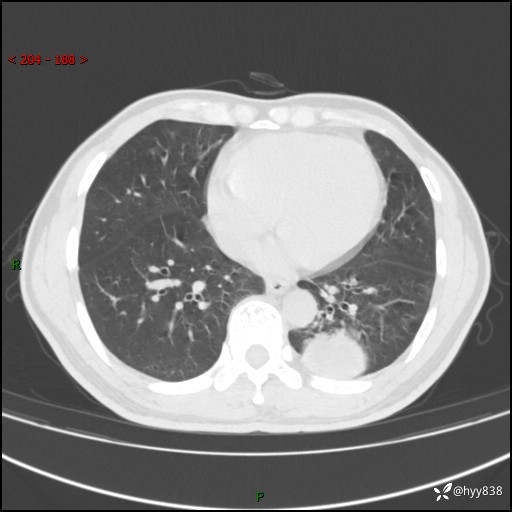

57岁/男,间断痰中带血1月余。纤支镜没有取到东西,穿刺轻松搞定---结果公布~

现病史:患者1月余前无明显诱因出现咯血症状,为痰中带血,量不大,伴轻度咳嗽,2024-3-26于当地市中医医院行胸部CT示:左肺下叶占位性病变。现患者仍有咳嗽不适,无发热乏力,无腹泻、便秘,无咳嗽,无头晕、无双下肢水肿等伴随症状,未行特殊治疗,今日患者再次出现咯血症状。患者为求进一步诊治,遂入我院,门诊以“肺脓肿”收入我科。 患者病程中,精神食欲可,二便正常,体力体重较前变化不明显。

增强

下肺占位,穿刺明确病理

治疗:手术或其它保守治疗